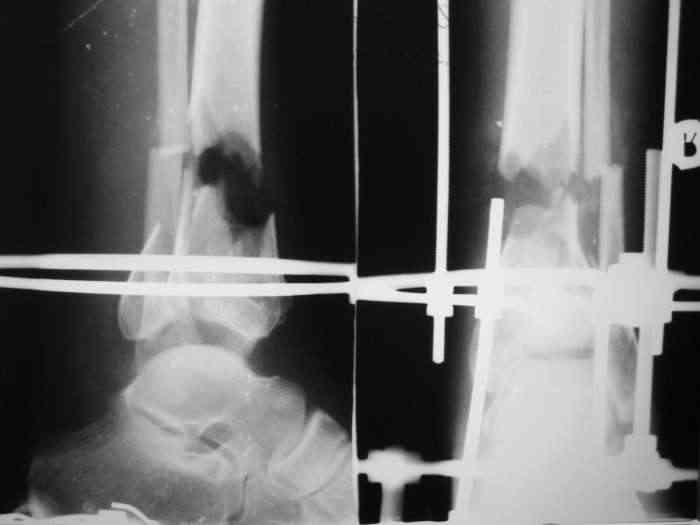

В понедельник в операционной выполнена санация раны с резекцией всех участков кости выступающих в просвет раны, удалены свободнолежащие фрагменты, некрэктомия. Промыто и заполнено салфеткой с некролитической мазью. Дополнительно проведена спица в с/3 голени. "Вытянул" голень до анатомичекой длины. После операции получил неприятный "сюрприз" - дистальный фрагмент б/б кости "разнесло". Снимки выложу завтра. Думаю опять ослабить дистракцию с целью собрать "в кучку" отломки дистального фрагмента, а также для

уменьшения раневой полости (которая меня, по-правде говоря, ужасает).

При закрытой попытке поймать и собрать отломки дистального фрагмента спицами с напайками, удача покинула меня.:-(

Срепонировать суставную поверхность мне не удалось. Только зря прошил ткани, а отломки остались в прежней позиции. Так и подмывало провести спицу через ахилл ... или пойти открыто задним доступом и притянуть винтом. Но смущает один момент: на чем будет держаться резьбовая часть винта, если передная поверхность разбита в хлам? Винт будеть елозить и не даст должной копрессии. Есть ли резон, при нынешнем состоянии раны, пойти на открытую репозицию заднего отдела суставной поверхности?

На мой взгляд необходимо уменьшить дистракцию до полного сближения отломков.Не видно,что в ране-возможно стоит произвести ревизию с тщательной санацией,секвестрэктомией(почти наверняка без этого не обойтись)-судя по снимкам идет воспалительная резорбция концов отломков.

Стояние отломков неплохое,может быть лучшее враг хорошего?

Возникшее расхождение отломков дистального метафиза наиболее вероятно связано с дистракцией в аппарате - лигаментотаксис : задняя тиб.фиб. связка *утянула* задний фрагмент.

Уменьшите дистракцию - всё вернется на свою предыдущую позицию, фиксируйте метафизарные фрагменты спицами 2-3-4 в разных направлениях.